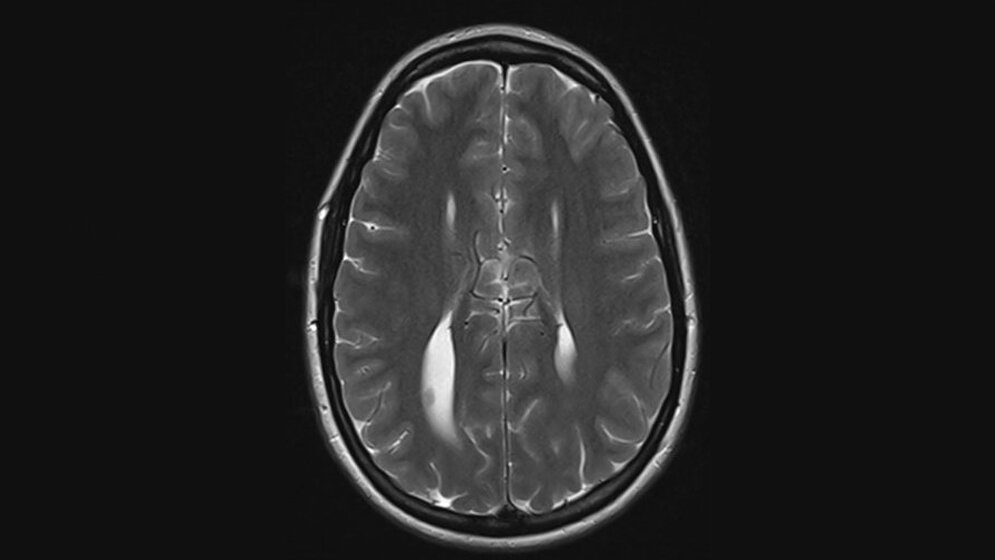

Die Kolpozephalie ist eine angeborene Malformation des Ventrikelsystems des Gehirns. Die Balkenagenesie kann isoliert vorkommen oder in Assoziation mit anderen neuroanatomischen Veränderungen beziehungsweise angeborenen Anomalien.

Schlüsselwörter: Kolpozephalie, Dysgenesie des Corpus callosum, CT, MRT